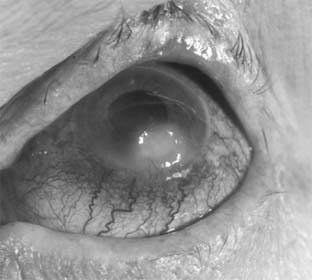

Fungal ulcers are indolent and have a gray infiltrate, often a hypopyon, marked inflammation of the globe, superficial ulceration, and satellite lesions (usually infiltrates at sites distant from the main area of ulceration) (Figure 6-3). The principal lesion-and often the satellite lesions as well-is an endothelial plaque with irregular edges underlying the principal corneal lesions, associated with a severe anterior chamber reaction and a corneal abscess.

Figure 6-3

Figure 6-3: Corneal ulcer caused by Candida albicans.

Most fungal ulcers are caused by opportunists such as Candida, Fusarium, Aspergillus, Penicillium, Cephalosporium, and others. There are no identifying features that help to differentiate one type of fungal ulcer from another.